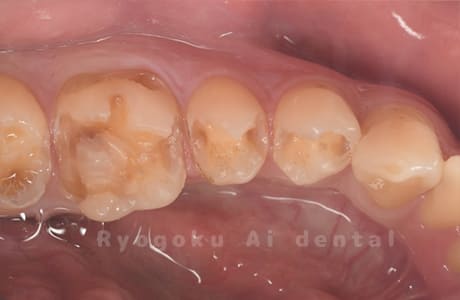

Case22

-

- 原因

- インレー2次カリエス

- 治療内容

- 左上6番→ダイレクトボンディング

左上7番→セラミックインレー

- 治療費用

- ダイレクトボンディング66,000円

セラミックインレー77,000円

奥歯の銀歯を白くしたいとのことでご来院された患者様です。経過良好です。

<リスク・副作用>

治療中もしくは治療後に急に痛みが出る場合があります。感染が強い場合には痛みが激しいことがありますので、その際は痛み止め、抗生剤を処方する場合があります。

また、ダイレクトボンディングは強い衝撃などにより欠けたりすることがある。経年的に劣化(変色)してくる可能性がある。